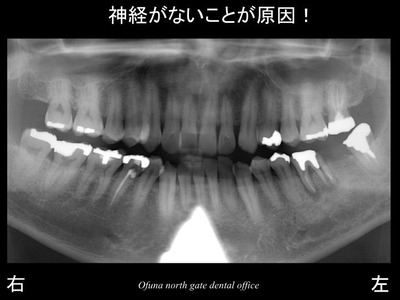

以下は、初診時のレントゲンです。

下顎左側の奥歯が腫れるとのことで来院されました。

歯根破折 です。

歯根破折 についてはこのブログでも頻繁に出てくるケースですので、お分かりの方も多いかと思います。

始めてこのブログを読まれる方のために

簡単に神経のない歯について解説します。

神経のない歯は もろく 通常の咬む力でも割れてしまうことがあります。

こうした状態を患者さんに説明する時に”木”に例えてお話しすることがあります。

生き生きとした木はたたいたり、蹴ったりしても折れたりすることはありませんが、

枯れた木は折れる可能性があります。

神経を取った歯も枯れた木と同じような状態になります。

神経のない歯は血液供給がなくなるためもろくなってしまうのです。

今回の症例も神経がない歯が折れたのです。

以下の赤丸は神経がない歯です。

本当に神経がない歯は問題が多いです。

みなさんも神経を取らないように 虫歯には気をつけましょう!